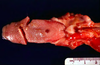

Ferret adrenal neoplasm

Signs due to hyper- estrogenism

Alopecia

(appears bilaterally symmetrical)

PU/PD

Vulvar enlargement

Anemia

Endometrial/prostatic hyperplasia

Cortisol normal